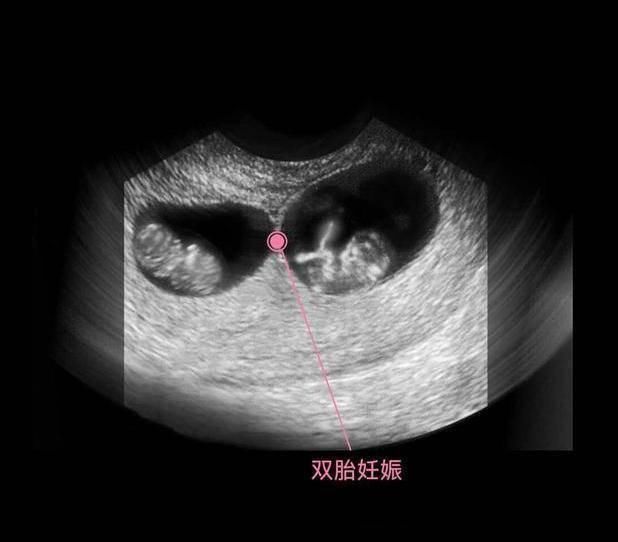

文章插图

在上图可见是个双胎妊娠,胎儿具有一个很大的头,和身材很不对称,是不是跟出生后的胎宝宝有点像了?其实此时的头部比例更悬殊,宝宝的额面部器官发育很明显,心脏也开始了跳动,出现了胎心,此时做B超,可见胎心胎芽。